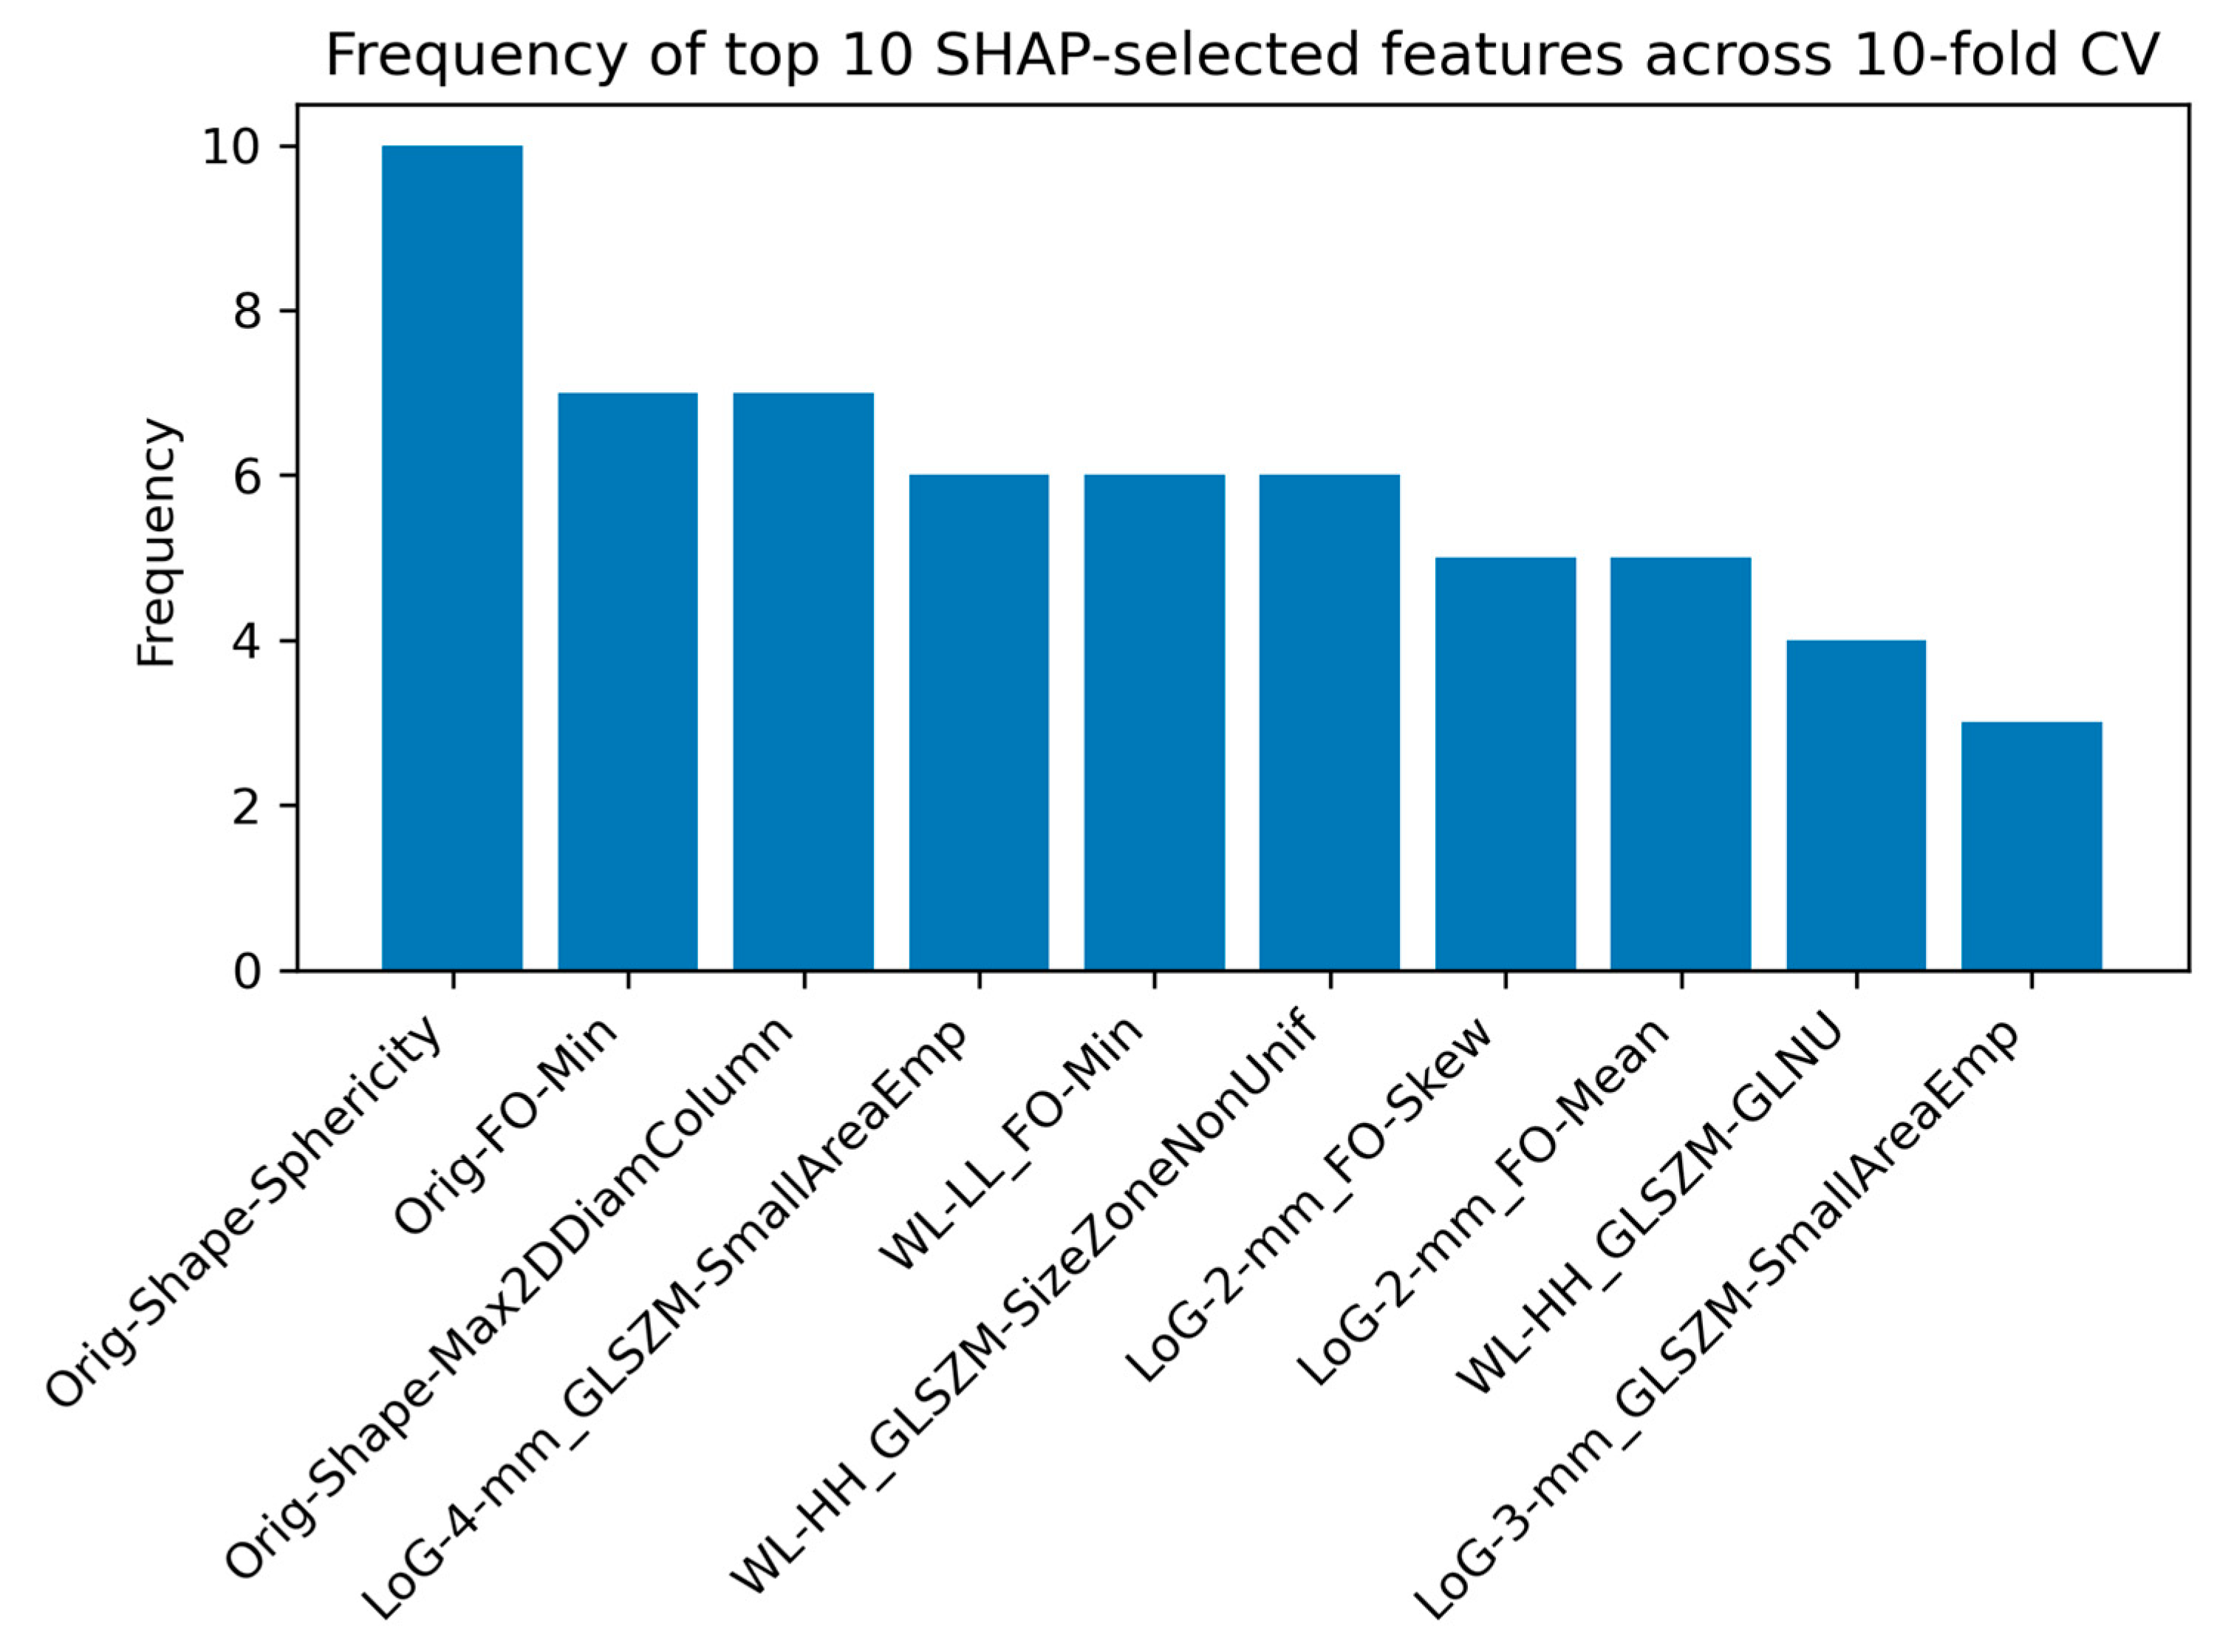

2.2.5. SHAP Analysis for Feature Interpretability

3.3. Results for the LGG-HGG-MET-MEN Classification Task

4.4. Interpretation of Radiomic Features Using SHAP Analysis